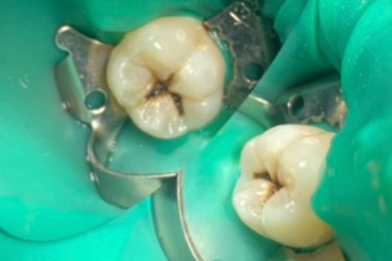

Лечение кариеса на зубе 37, 36 «скрытая кариозная полость на зубе 36»

Колиш Максим Петрович -